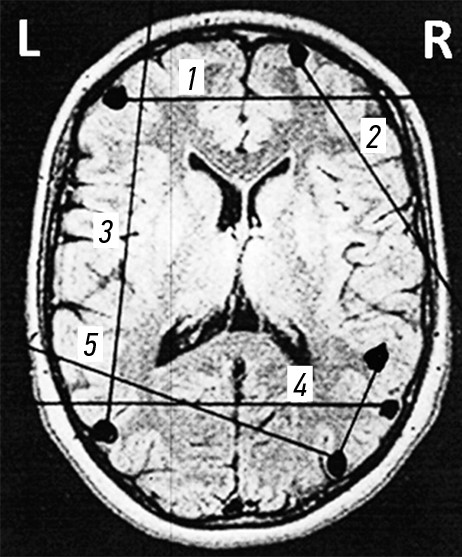

Ходы раневых каналов при огнестрельных проникающих осколочных ранениях черепа и ГМ, также примеры диагнозов продемонстрированы на рис. 3–7.

Рис. 3. Огнестрельные проникающие слепые простые и радиальные ранения черепа и головного мозга. Примеры диагнозов: 1 — минно-взрывное ранение (МВР). Огнестрельное осколочное слепое проникающее простое ранение правой лобной доли головного мозга; 2 — МВР. Огнестрельное осколочное слепое проникающее радиальное ранение правой лобной доли головного мозга; 3 — МВР. Огнестрельное осколочное слепое проникающее радиальное двуполушарное ранение левой теменной доли головного мозга.

Рис. 4. Огнестрельные проникающие сегментарные ранения черепа и головного мозга. Примеры диагнозов: 1 — минно-взрывное ранение (МВР). Огнестрельное осколочное слепое (сквозное) проникающее двуполушарное сегментарное ранение лобных долей головного мозга; 2 — МВР. Огнестрельное осколочное слепое (сквозное) проникающее сегментарное ранение правой лобной доли головного мозга; 3 — МВР. Огнестрельное осколочное слепое (сквозное) проникающее сегментарное ранение левой лобной и теменной доли головного мозга; 4 — МВР. Огнестрельное осколочное слепое (сквозное) проникающее двуполушарное сегментарное ранение теменных долей головного мозга; 5 — МВР. Огнестрельное осколочное слепое (сквозное) проникающее сегментарное двуполушарное рикошетирующее ранение левой теменной и правой затылочной доли головного мозга.